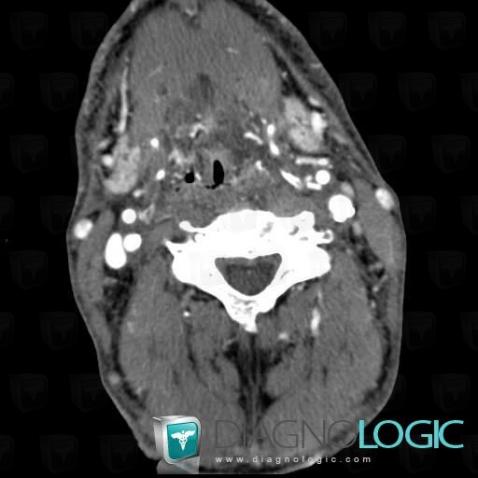

Postradiation edema, Oropharynx / Floor-mouth, CT

Here is the specific information in the key image above:

- Diagnosis Postradiation edema, Location(s) Oropharynx / Floor of mouth, with gamuts